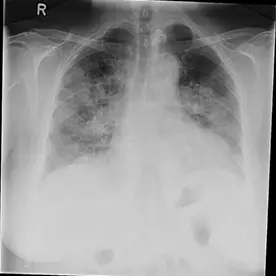

COVID-19 Pneumonie

61-jährige Patientin mit Z. n. Apoplex, fieberhafter bronchopulmonaler Infekt

Es zeigen sich bipulmonale konsolidierende Infiltrate ohne begleitende Pleuraergüsse. Bei positivem Test der Patientin auf COVID-19 ist hier von einer COVID-19-Pneumonie auszugehen.

Covid-19 Pneumonie (SARS-CoV-2)